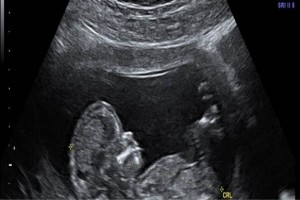

El programa fue diseñado para llevar de la mano al participante y ofrecerle herramientas que le permitan hacer una evaluación radiológica atinada, lo cual lo llevará a un diagnóstico que por ende arrojará el tratamiento idóneo. El énfasis se ha dado en la metodología diagnóstica, que es por inducción, así como el manejo del paciente, para crear una conciencia responsable y humana entre los que se dedican o quieren iniciarse en la práctica de la ultrasonografía. Dado a que existe una aplastante demanda de estudios de ultrasonido ante el insuficiente número de médicos radiólogos certificados, además de que el servicio de rayos x en México ha sufrido de ineficiencia en la aplicación del estudio y elaboración diagnóstica de la patología, la labor de este curso es formar de manera profesional a los médicos para que cubran y aminore en gran medida este problema que habita en el sector de salud.